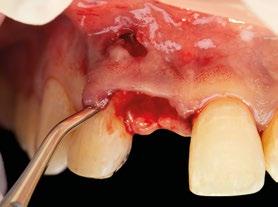

5.- Tunelizamos el defecto vestibular para alojar el injerto de tejido conectivo. (Figura 18)

6.- Colocamos injerto de tejido conectivo. (Figura 19)